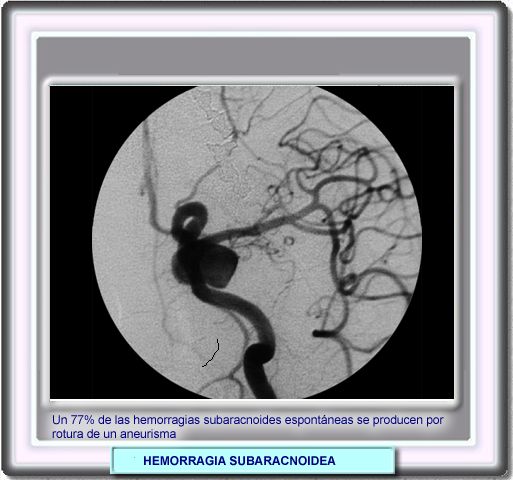

HEMORRAGIA

SUBARACNOIDEA

La mayor parte de las hemorragias subaracnoideas no traumáticas se producen por ruptura de un aneurisma. De estas aproximadamente, el 85% se produce por la ruptura de alguno situado en la parte inferior del polígono de Willis. Los aneurismas gigantes de más de 2 cm de diámetro aparecen en las mismas localizaciones que los de menor tamaño. Las tres localizaciones más frecuentes son la arteria carótida interna intracraneal, la bifurcación de la arteria cerebral media y la parte superior de la arteria basilar El saco aneurismático es histológicamente una pared arterial adelgazada, de tejido fibroso con solo la capa íntima y la adventicia, sin componente muscular con disgregación y rotura de las capas de fibras elásticas. Se atribuye el aneurisma a un estrés hemodinámico y a la hipertensión arterial. |